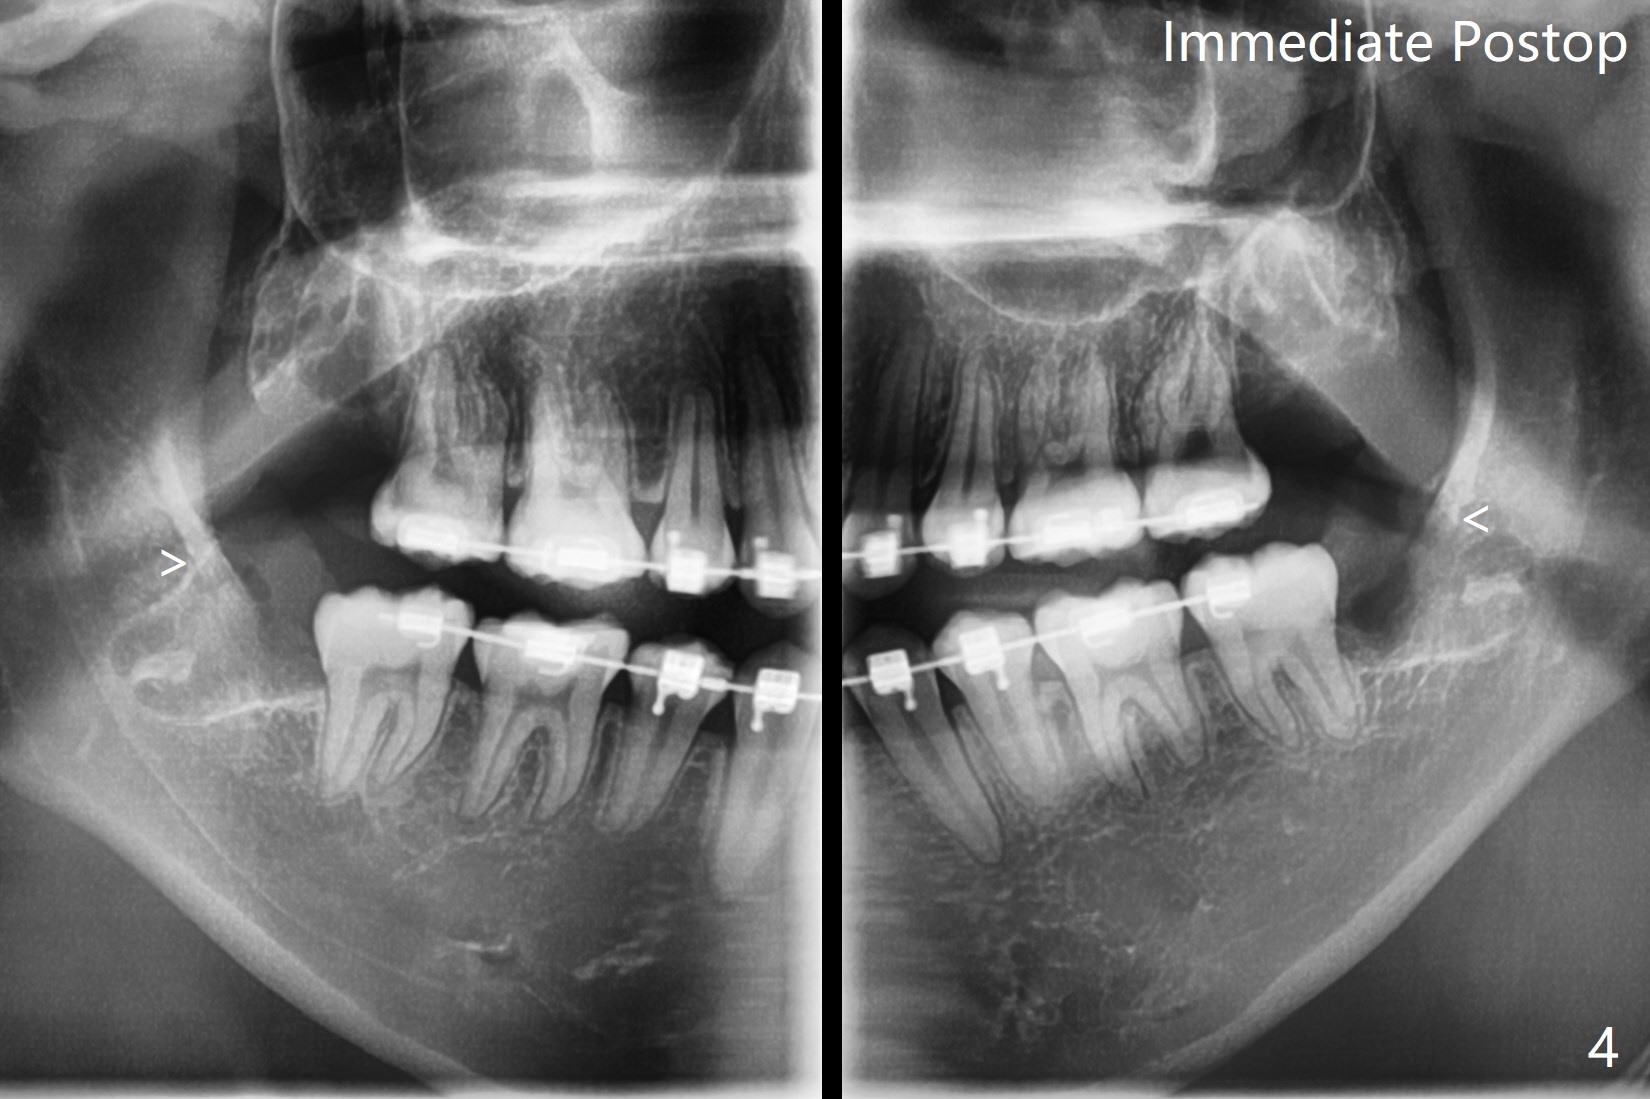

17岁女孩3年前拍摄全景片后拔除4个第一双尖牙(图一),在别的诊所进行矫正(图二,三),在局麻下拔除4个智齿,由于去骨,显得外斜嵴缺失(图四:箭头),放置胶原塞(防止干槽症),4-0含铬羊肠线缝合,预计外斜嵴6-12月能修复。